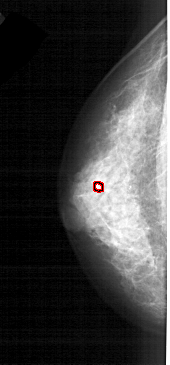

A_1609_1.LEFT_CC

LEFT_CC LINES 4006 PIXELS_PER_LINE 1861 BITS_PER_PIXEL 12 RESOLUTION 43.5 OVERLAY

FILE: A_1609_1.LEFT_MLO.OVERLAY

TOTAL_ABNORMALITIES 1

ABNORMALITY 1

LESION_TYPE CALCIFICATION TYPE PLEOMORPHIC DISTRIBUTION CLUSTERED

ASSESSMENT 4

SUBTLETY 2

PATHOLOGY BENIGN

TOTAL_OUTLINES 1

FILE: A_1609_1.LEFT_CC.OVERLAY